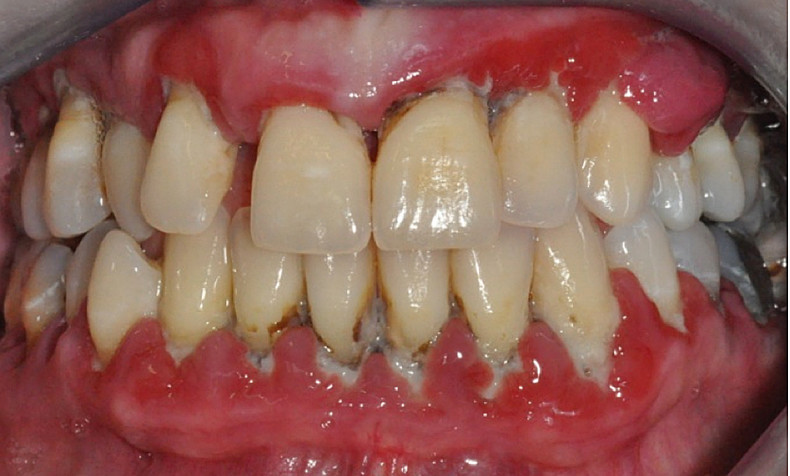

Paradentóza je závažné chronické onemocnění, které dnes v České republice postihuje téměř každého dospělého člověka.

Její příčinnou je působení mikroorganismů, jejichž množení podporuje zubní plak a zubní kámen a které v konečném důsledku může vést až ke krvácení dásní a vypadávání zubů.

V současné době neexistuje žádný prostředek, kterým by bylo možné tyto mikroorganismy hubit, jedinou cestou, jak se paradentóze bránit, tak zůstává prevence a důsledná hygiena.